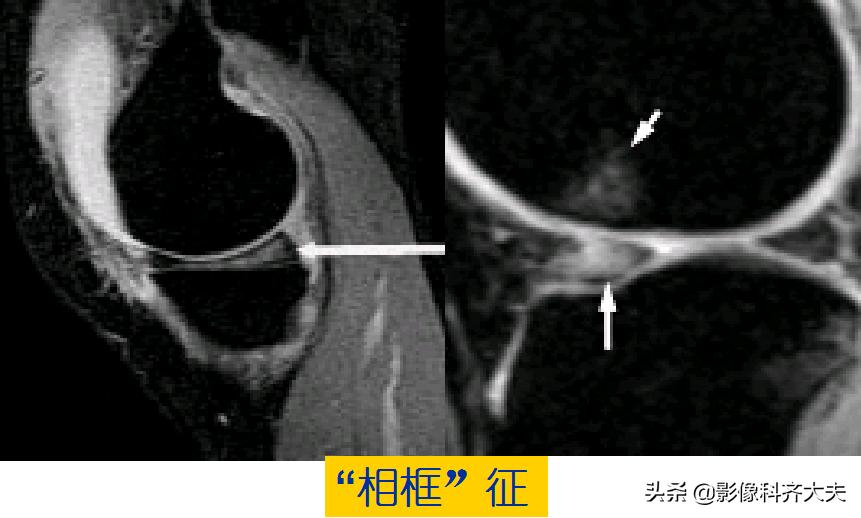

容易误诊为半月板损伤的正常解剖结构

内侧半月板后角上隐窝: